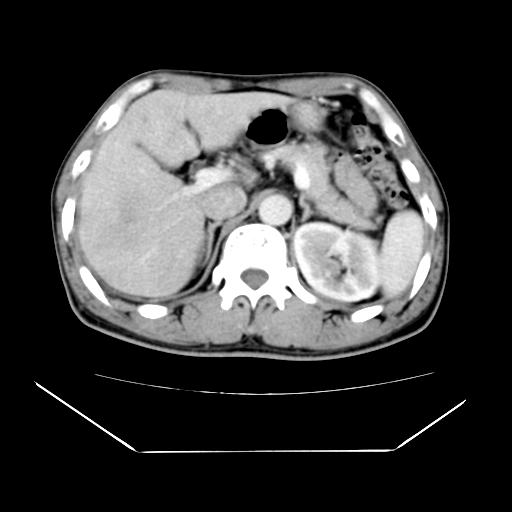

男性,55岁,外院体检afp明显升高,但b超未发现异常,否认乙肝病史。来我院ct增强。有延时扫描。

延时扫描完全充填,血管瘤

肝脏右叶动脉期可见低密度影,至延迟期被充填,考虑血管瘤可能性大。

肝右叶病灶

不排除肝右叶肝癌可能。

这个不是肝右静脉吗,这么大的病灶b超不可能发现不了吧

如果这个是癌灶的话则下腔静脉有瘤栓可能

肝6段血管瘤

血管瘤可能性大。

是肝右静脉吧

考虑肝右静脉影。